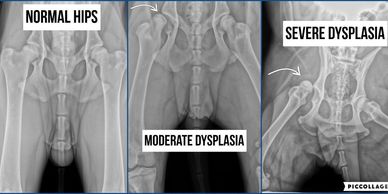

Puppies raised on slippery floors have a 60% greater chance of developing hip dysplasia. While genetics obviously play a big part in this area, environment has its role as well. We are doing all we can on our end to make sure your puppies' parents have genetically healthy hips.

Providing them with a suitable environment to grow and develop safely is up to you! Once your puppy's hips, muscles, ligaments have completely developed (in a good environment with proper traction) then slippery floors are LESS dangerous for him/her.